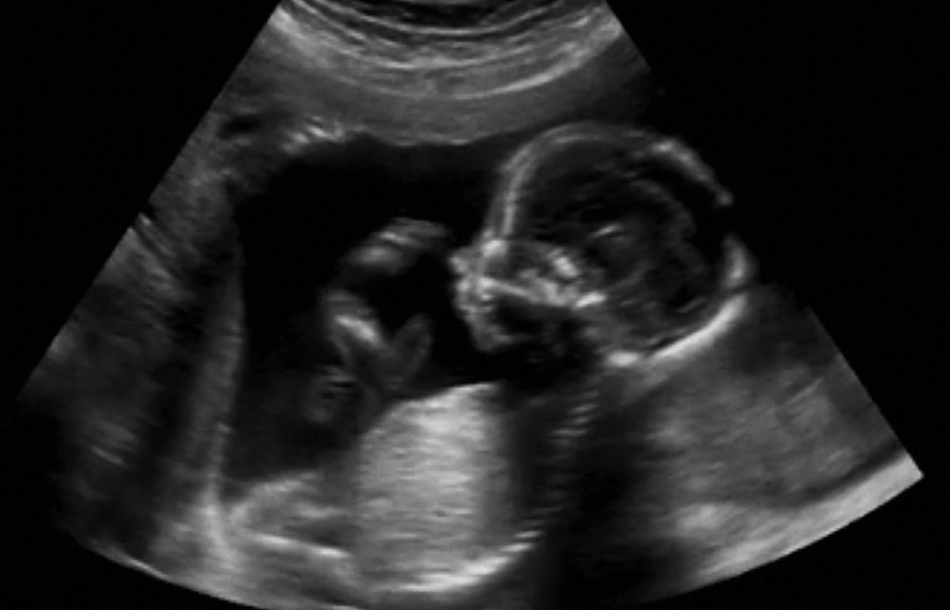

is a useful tool used for scanning fetus, fetal structures, placenta and amniotic fluid during pregnancy. It can be performed via a trans-abdominal or trans-vaginal approach depending on the pregnancy trimester and condition.

For more information on this ultrasound modality please refer to " pelvic Ultrasound" under "Medical Information" section.